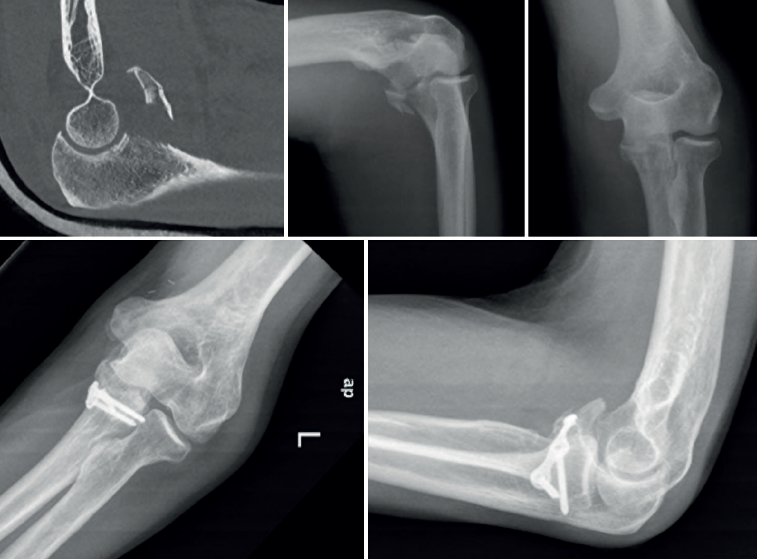

- Radiografía simple: las radiografías anteroposterior y lateral, antes y después de la reducción, son fundamentales para evaluar la congruencia articular y la presencia de fracturas (Figura 1).

- Tomografía axial computarizada (TAC): en especial la reconstrucción 3D, que nos permite evaluar con detalle las fracturas. En el caso de la cabeza radial, su extensión y conminución, y en cuanto a la apófisis coronoides, su tamaño. De esta manera, la TAC permite una adecuada planificación preoperatoria, decidiendo aspectos como el abordaje o el tipo de osteosíntesis(7)(Figura 2).